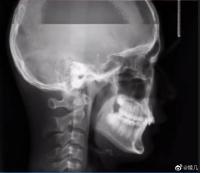

拍牙片時打了個哈欠,變成了毒液?用3D打印技術(shù)制作牙齒的好處

小編看到牙片表示:恐怖片果然來源于生活。有網(wǎng)友會問3D打印技術(shù)能制作牙齒嗎?小編告訴你:可以!那么用3D打印技術(shù)做牙齒有哪些好處呢?